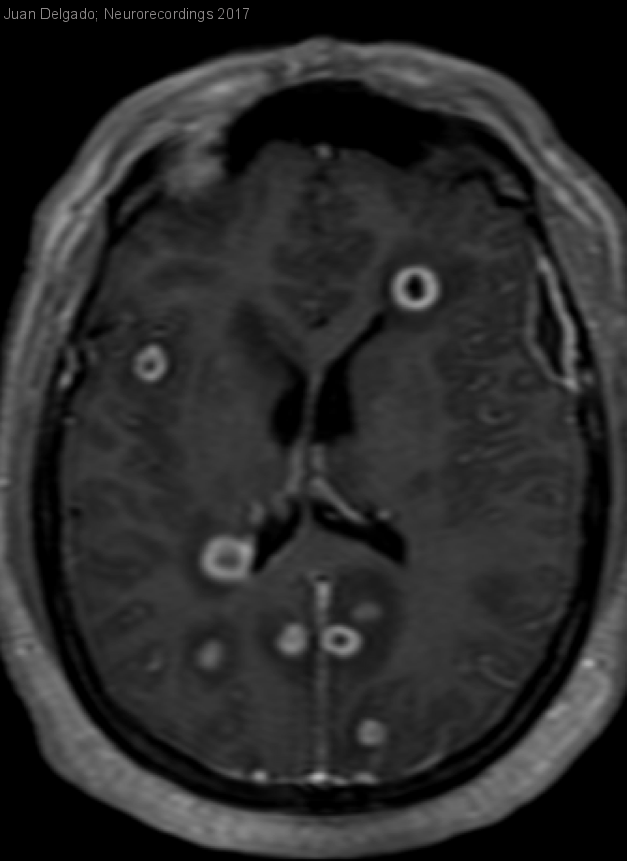

Abscesos cerebrales múltiples

Abscesos cerebrales múltiples

Hombre | 32 años

Diagnóstico final: Abscesos cerebrales múltiples

Varón de 32 años con antecedentes de síndrome de apnea obstructiva del sueño y neumonías de repetición. El alta del último ingreso por neumonía se produjo hace aproximadamente una semana. Acude a urgencias por cefalea...